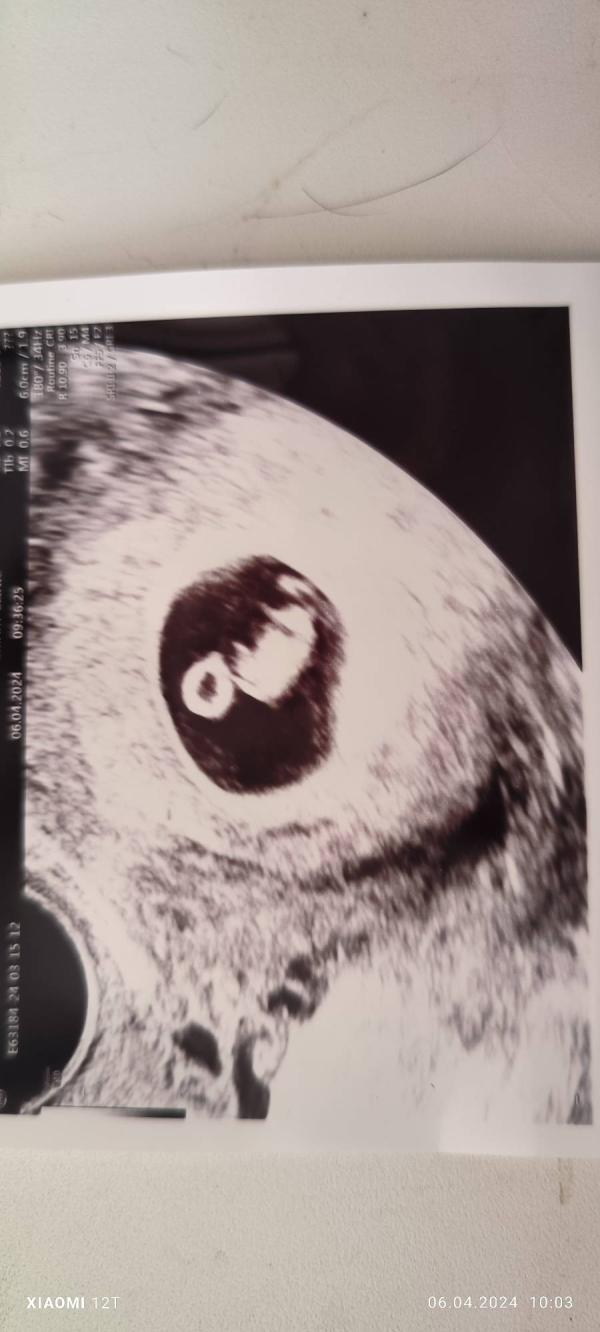

7 недель и 3 дня: ЧСС 163, малыш 12 мм!

Срок 7 нед 3 дн

ЧСС 163

И целых 12 мм

06.04.2024